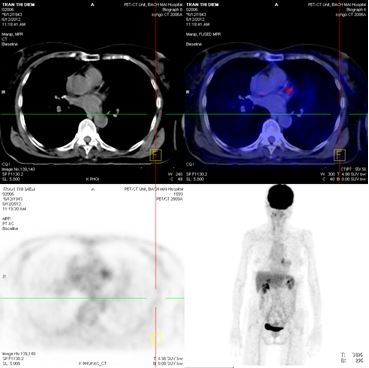

Chụp PET/CT:

Hình 4: Hình ảnh PET/CT có khối u thùy dưới phổi phải 2,6 × 2,8 cm, Max SUV= 5,32

Hình 5: Hình ảnh PET/CT có tổn thương cung sau xương sườn số 5 bên trái, và khối u não vùng đỉnh trái

Chụp PET/CT toàn thân sau 6 tháng điều trị:

Trước điều trị : Khối u thùy dưới phổi phải 2,6 × 2,8 cm, Max SUV = 5,32

Sau điều trị 6 tháng: U tan gần hoàn toàn

Hình 7: Hình ảnh PET/CT toàn thân sau 6 tháng điều trị: Khối u phổi tan hoàn toàn

Trước điều trị: tổn thương thùy đỉnh trái 2 cm

Sau điều trị 6 tháng: tổn thương tan hoàn toàn

Hình 8: Hình ảnh PET/CT toàn thân sau 6 tháng điều trị: Khối u não vùng đỉnh trái tan hoàn toàn.

Trước điều trị: Tổn thương cung sau xương sườn số 5 bên trái